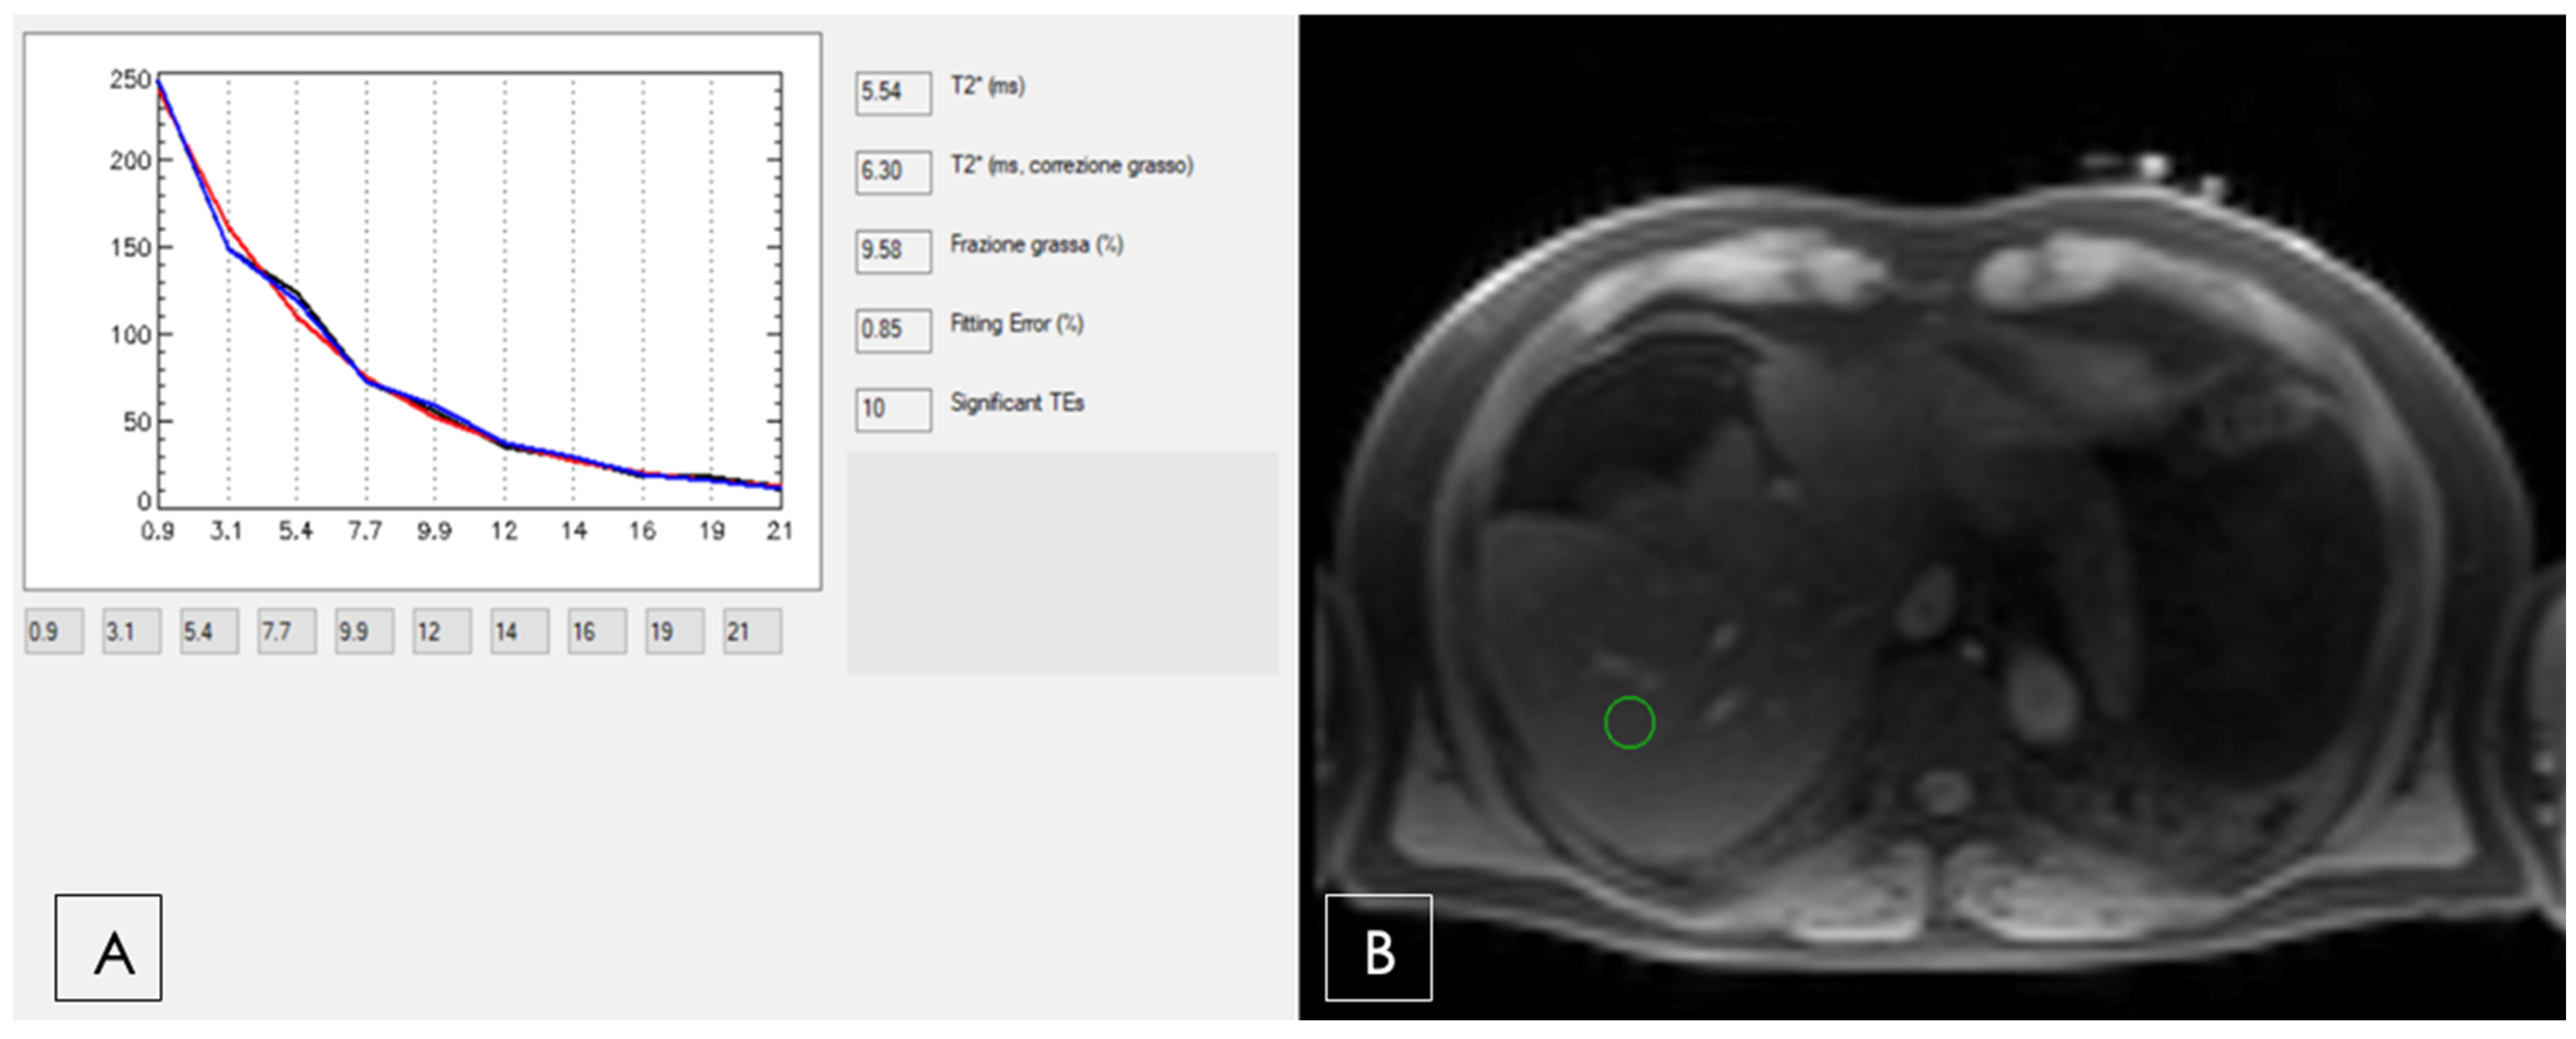

4.1. Diffuse Liver Diseases

4.1.5. Magnetic Resonance Imaging